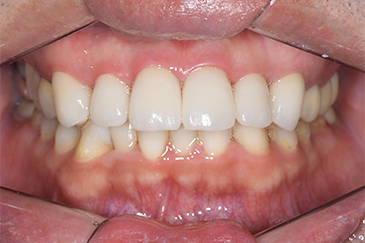

CASE 3

Before

After

基本情報

| 年齢・性別 | 30代・女性 |

| 主訴 | 定期検診 |

| 治療内容 | PMTC |

| 治療期間 | 60分 |

| 治療費 | 5,750円 |

| リスク・副作用 | しみる可能性があります。 |

| 治療方針 | PMTCでステインの除去。 |

| 担当者所見 | ステインが付きやすいため、3カ月毎の定期検診で除去する。 |